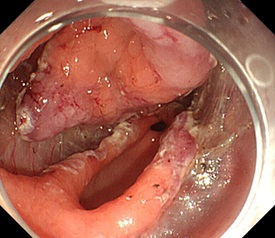

早期胃がんなどの消化管腫瘍の内視鏡切除(EMR/ESD)は、盛んに施行しています。総胆管結石を摘除する内視鏡的乳頭切除術(EST)や内視鏡的乳頭ラージバルーン拡張術(EPLDB)、経皮的胃瘻造設術(PEG)、食道静脈瘤結紮療法(EVL)なども行っています。

ESD |